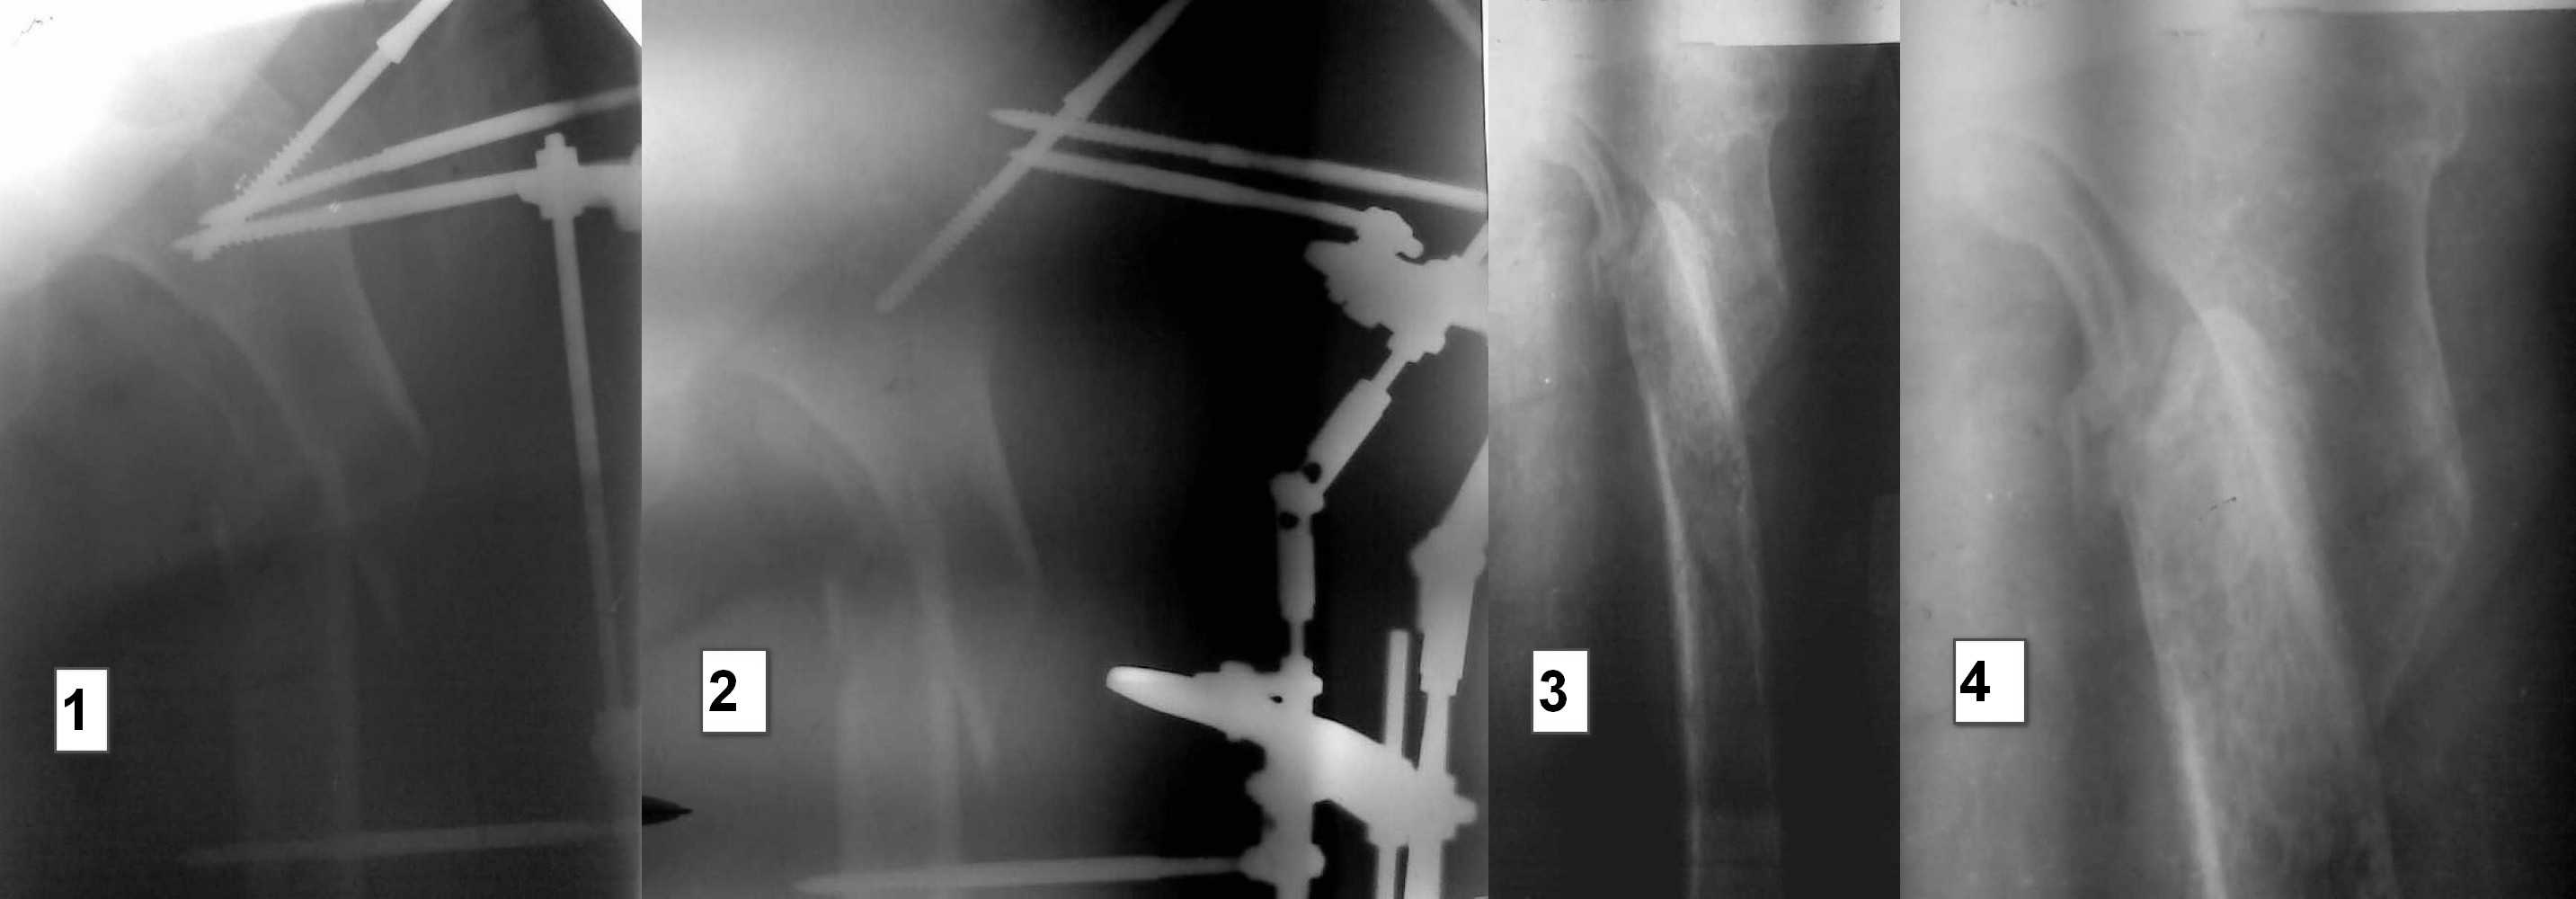

Доброго времени суток, уважаемые коллеги. Обратилась женщина 75 лет, с ложным суставом в/3

левого бедра. Ожирение 2-3 ст. Других серьёзных сопутствующих заболеваний нет. Со слов

больной - трава 10 месяцев назад, упала на левую сторону, перелом закрытый. Синтез в АВН,

выписана домой (снимок 1). Передвигалась на костылях без нагрузки на ногу, по прошествии 6

мес (снимок2) был выполнен демонтаж АВН, и дана команда ходить . В проксимальном отделе

эксудация уменьшается.(фото5). В проксимальном отделе бедра патологическая

подвижность. Больная садится в постели, опускает ноги. Свежие снимки фото 3-4 Планируем